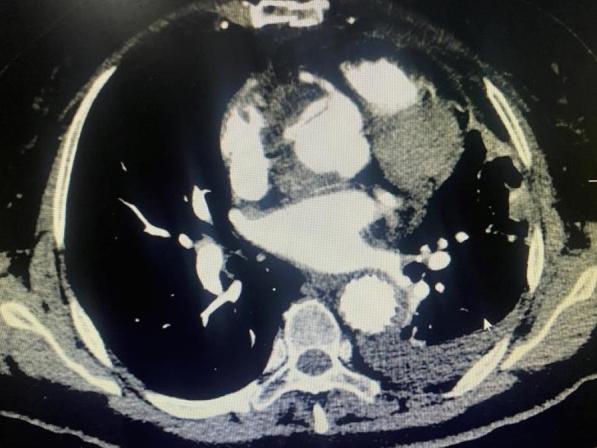

All 28 patients underwent successful surgery with a cardiopulmonary bypass (CPB) time of 265.0 (210.0-322.5) min, an aortic cross-clamping (ACC) time of 151.0 (112.0-209.0) min, and a drainage flow rate of 237.5 (126.0-297.0) mL at 12 h postoperatively. There were 2 (7.1%) perioperative deaths caused by renal failure, ischemia in 1 case, and coronary artery causes in 1 case. Postoperative complications included reopening of the chest for hemostasis in 1 case (3.6%) for reasons unrelated to the vascular anastomosis, hemodialysis in 3 cases (10.7%), paraplegia in 1 case (3.6%), and cerebral infarction resulting in impaired mobility of the left upper extremity in 1 case (3.6%). Tracheotomy was performed in 1 case (3.6%), and the duration of mechanical ventilation was 89 (48.0-165) h. Among the 26 recovered patients reviewed with aortic enhancement CT before discharge, the artificial vascular anastomosis had smooth blood flow, though 1 case still had residual entrapment in the sinus of the aorta.

In acute type A aortic dissection surgery, the "modified sandwich" technique using an artificial vascular sheet for aortic root shaping is simple, effective, and easy to master. This method can reduce anastomotic blood seepage and prevent anastomotic tear and bleeding, making it worth recommending for clinical application.